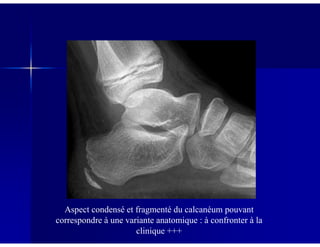

Aspect condensé et fragmenté du calcanéum pouvant

correspondre à une variante anatomique : à confronter à la

clinique +++